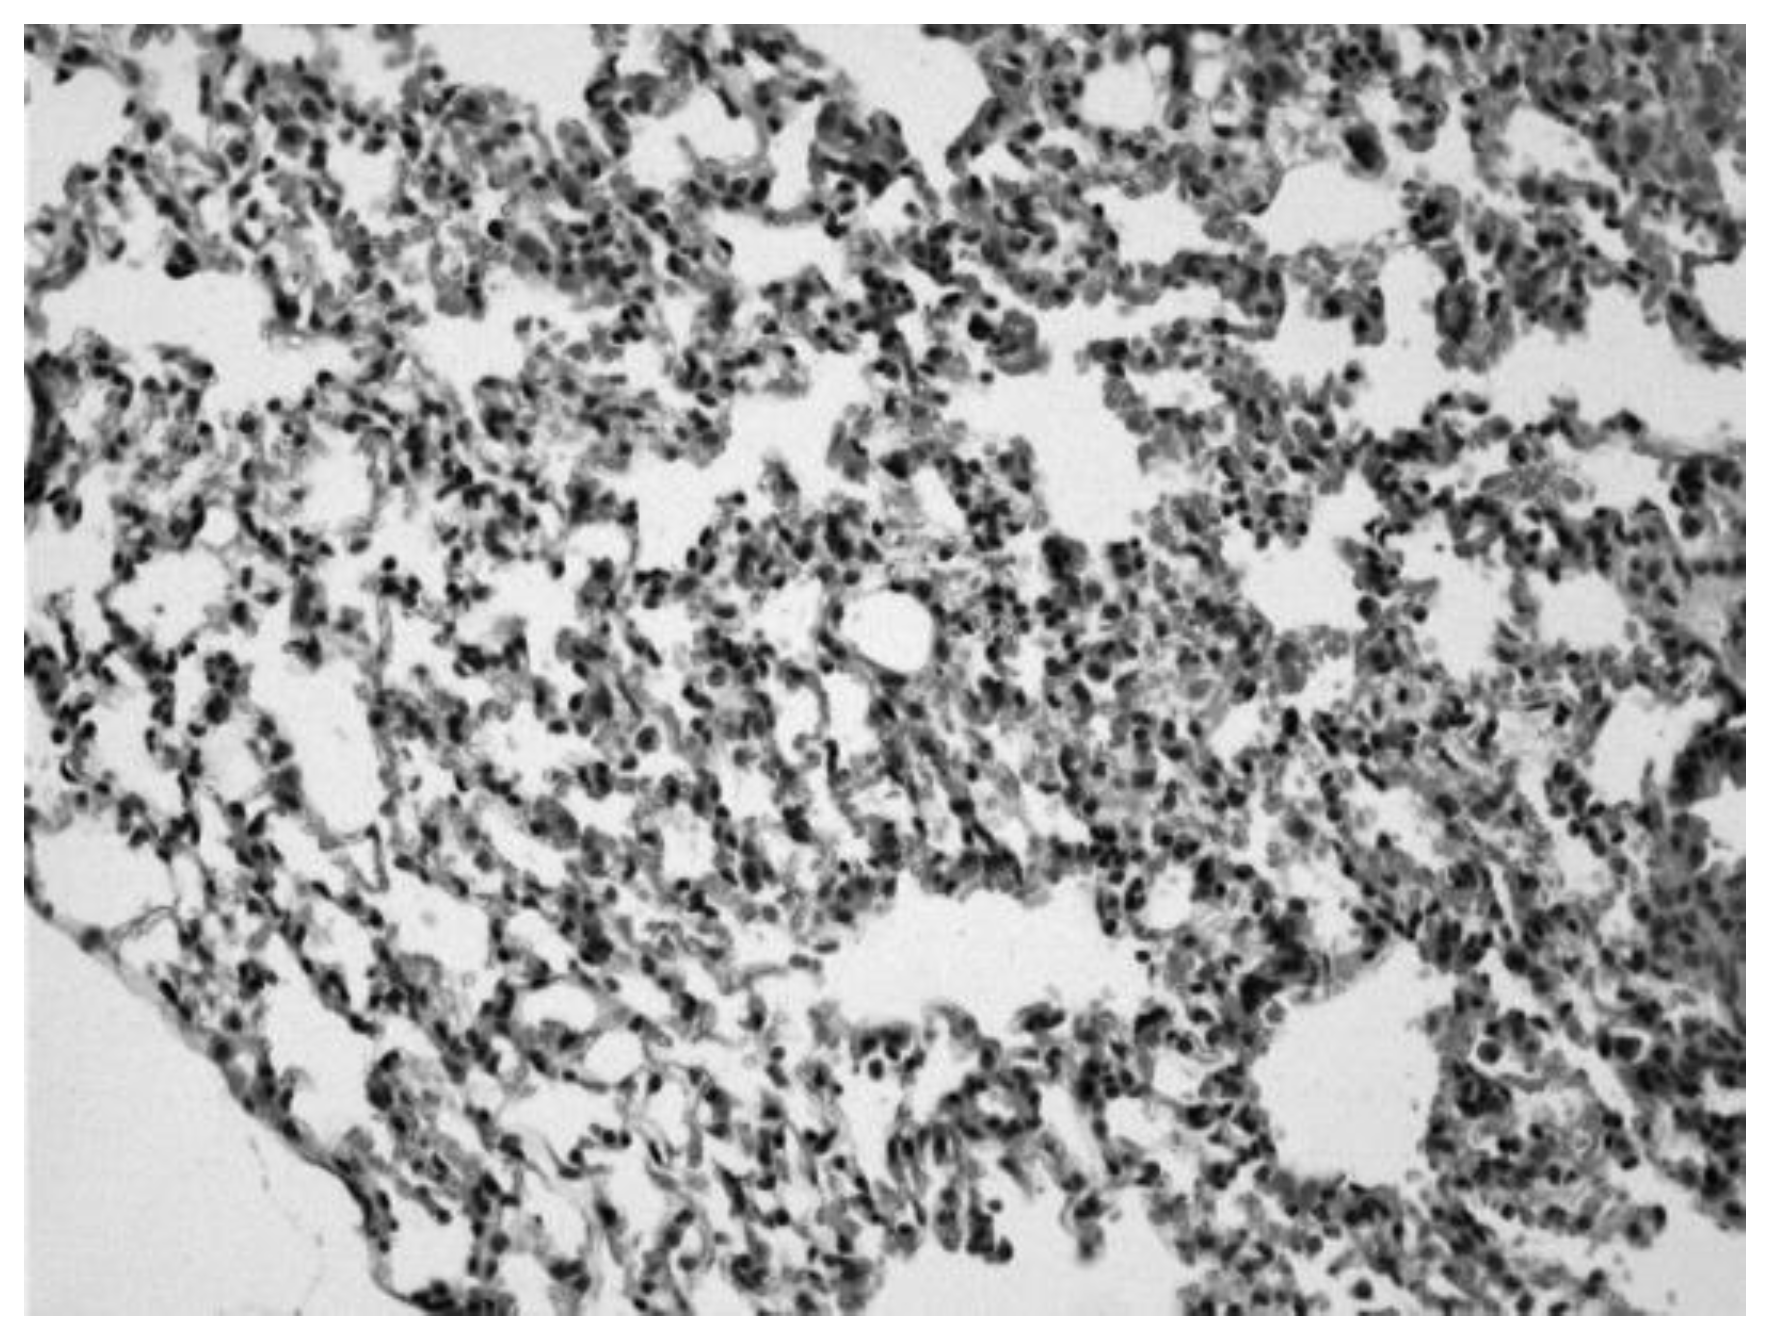

Image 2. Lung of an animal sensitized with ovalbumin in which we can observe infiltrates of inflammatory cells and erythrocytes in the alveolar spaces (Hematoxylin-eosin 20x).